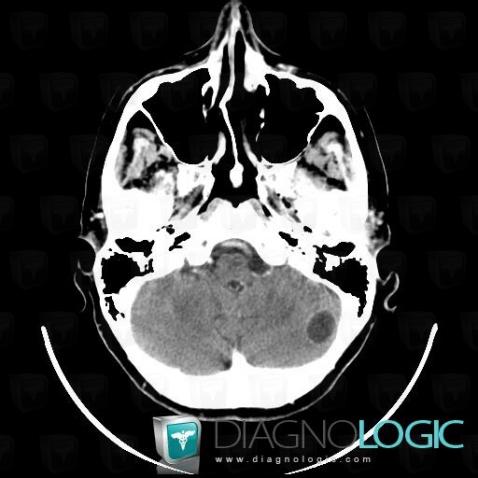

Metastasis, Cerebellar hemisphere, Posterior fossa, CT

Here is the specific information in the key image above:

- Diagnosis Metastasis, Location(s) Cerebellar hemisphere, with gamuts Cerebellar lesionPosterior fossa, with gamuts Infratentorial lesion with ring enhancement